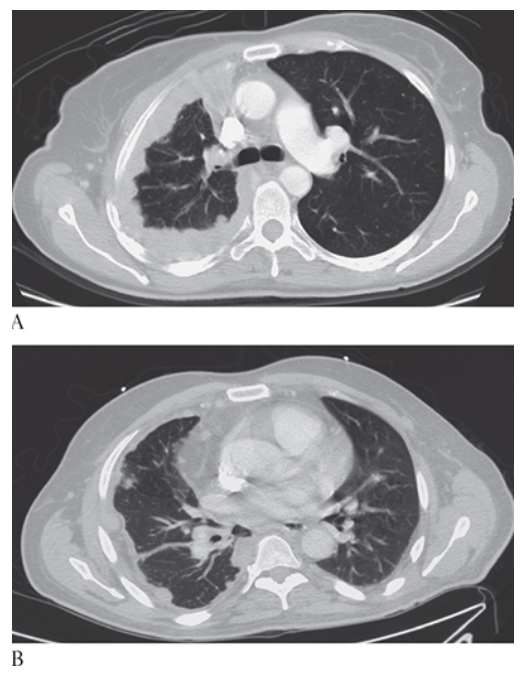

Sarcoidosis. HRCT shows increased opacification predominately involving the mid lung with peripheral nodules and atelectasis in the middle lobe and lingual.

Sarcoidosis. Mediastinal windows show densely calcified mediastinal and hilar lymph nodes consistent with sarcoid.